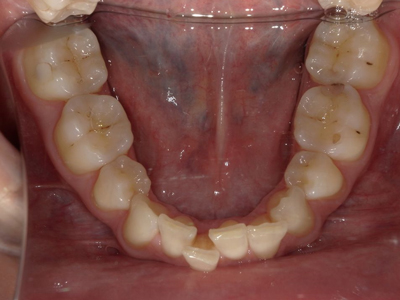

Arcade mandibulaire avant traitement orthodontique, séquelles de maladie parodontale

Après traitement orthodontique et réalisation d’une attelle fibrée (courtoisie Dr Patrick Fournier)